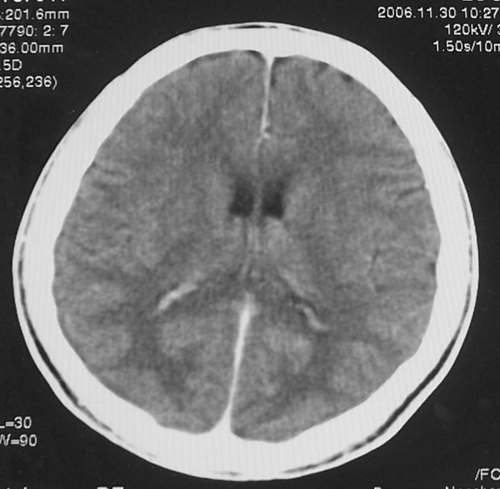

患者、男、18y,头痛5天入院。

左小脑、右丘脑区低密度影,无明显强化及占位表现,男18y,先考虑脑部炎性病变,如脑炎、血行播散性感染等,建议结合临床如脑脊液检验。

单独看左侧小脑半球的不规则形囊性低密度灶,从发病部位、年龄以及无强化、无占位效应的特点可以考虑毛细胞瘤型星形细胞瘤。同样,如果单独看右侧丘脑的近圆形低密度,也可以考虑囊变形星形细胞瘤。只是胶质细胞瘤一般为单发直接浸润、蔓延生长,而不是在脑内同时出现多个病灶,且瘤周没有一点儿水肿,暂时不予以考虑。

脑炎倒是首先可以考虑,只是临床症状、病史不很符合,建议狼兄仔细了解病史以及其他临床资料。

同时,现在已经进入冬天,一氧化碳中毒也需要考虑进去。不知道增强是什么时间做的,与平扫间隔几天?如果中间时间比较久而且进行吸氧等治疗,则平扫所示右侧颞叶密度比较低、右侧小脑半球以及脑桥也似有片囊状低密度,但在增强却没有发现就可以比较合理的解释了。